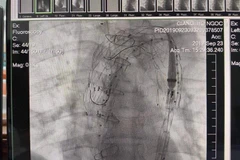

Ngày 12/10, lãnh đạo Bệnh viện Trung ương Huế (tỉnh Thừa Thiên-Huế) cho biết, một bệnh nhân nam 43 tuổi, trú tại tỉnh Quảng Bình, bị bệnh bóc tách động mạch chủ, vừa xuất viện.

Các bác sỹ Bệnh viện Đại học Y dược Thành phố Hồ Chí Minh phẫu thuật thành công cho một sản phụ mang thai 33 tuần, bị phình gốc động mạch chủ, rách động mạch chủ cấp.